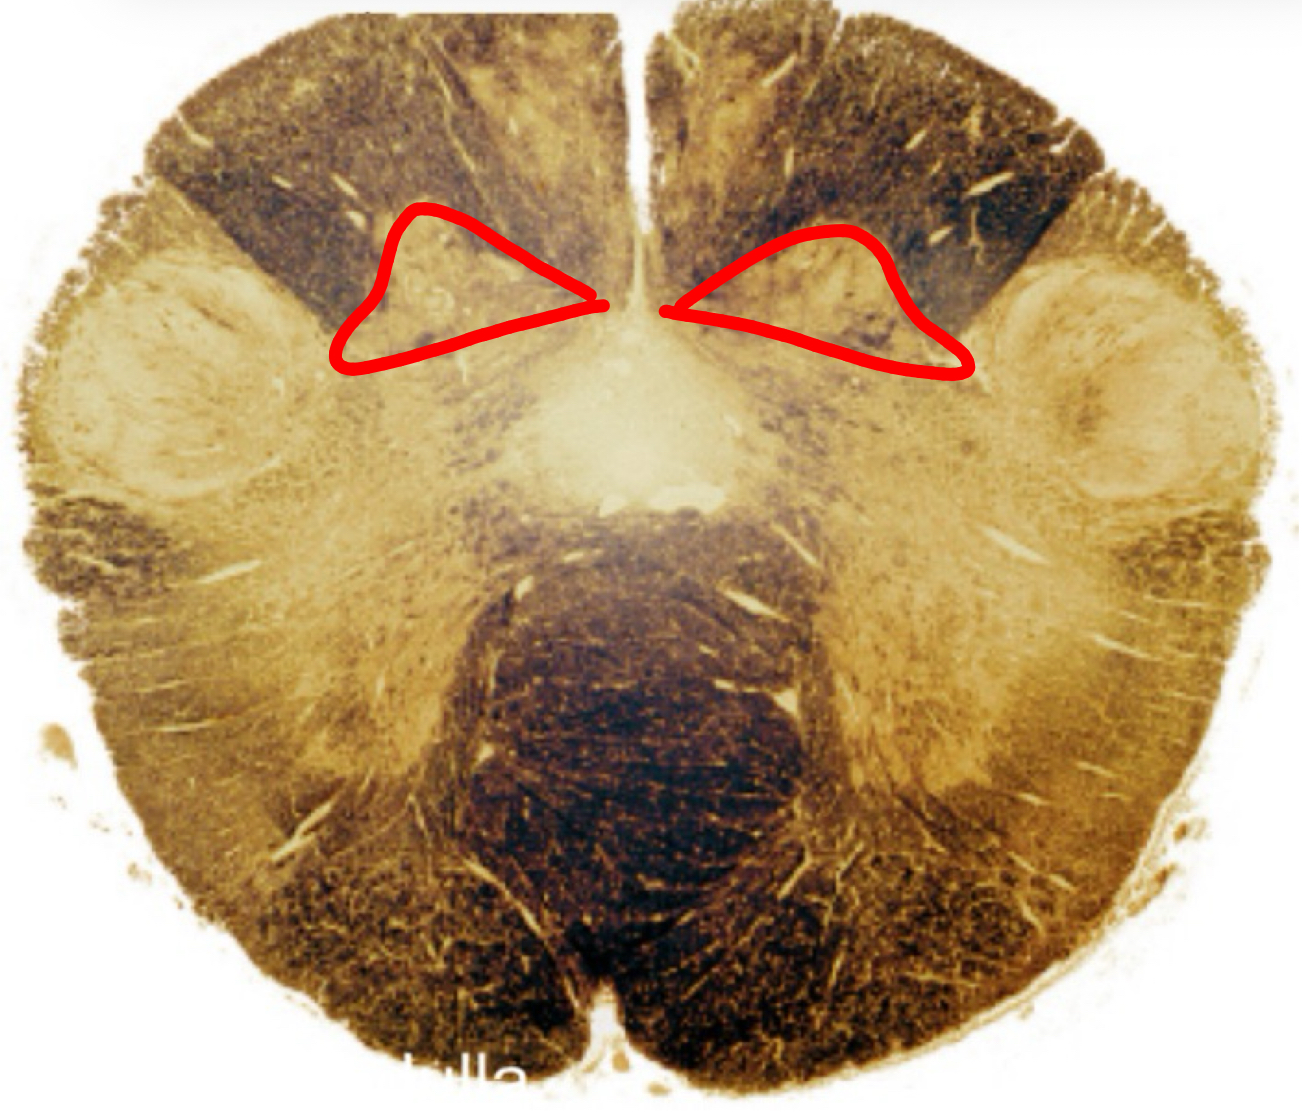

medial lemniscus rostral medulla